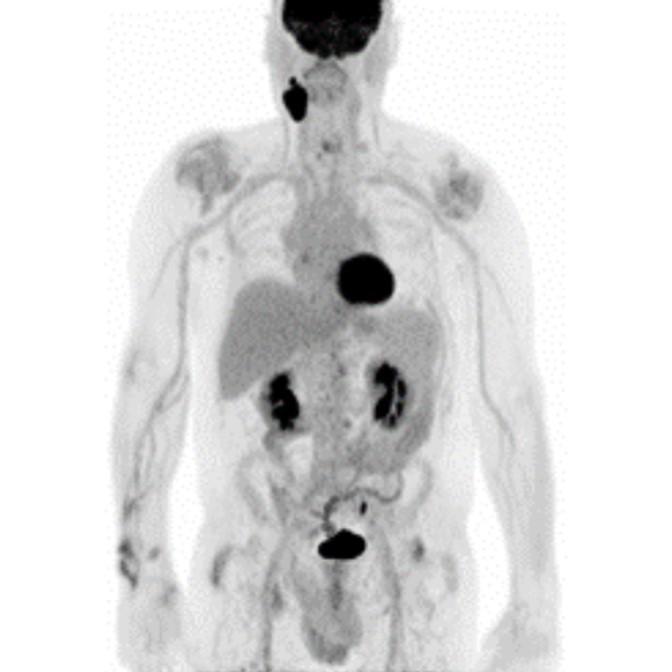

Partial nml and melanoma PET scan